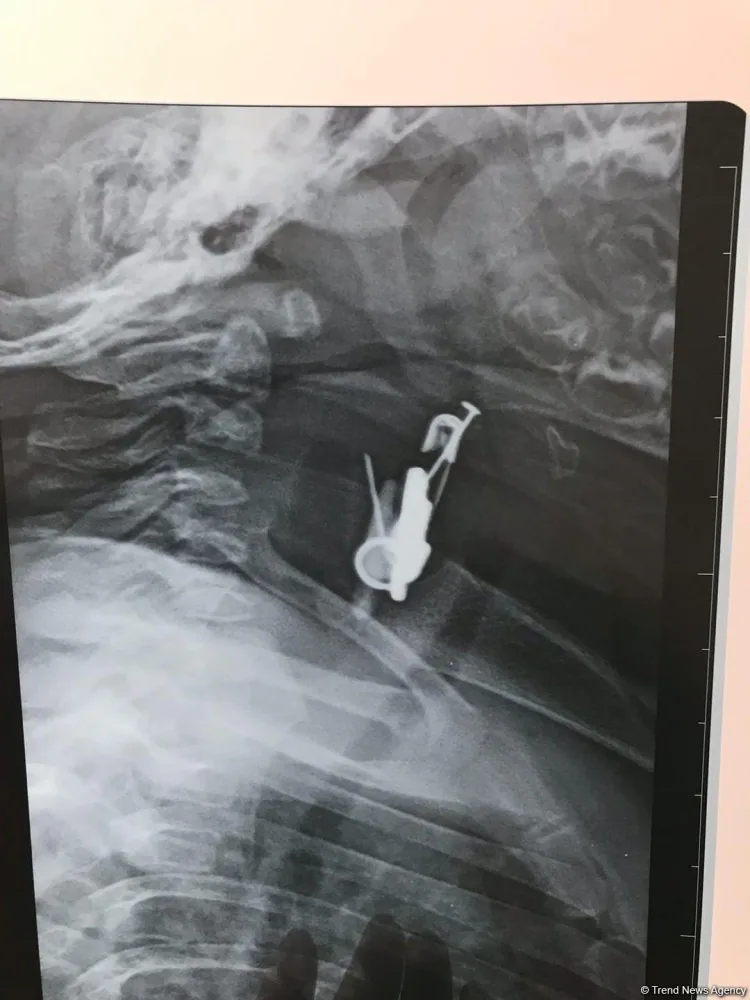

Azərbaycanda altı aylıq körpənin mədəsindən sancaq və digər cisimlər çıxarılıb.

News24.az Trend-ə istinadən xəbər verir ki, hadisə Biləsuvar rayonunda baş verib. Belə ki, sözügedən rayonda valideyn yeni doğulan oğlan uşağına gözdəyməyə qarşı daş və ələmi sancaqla onun paltarına taxıb. Bir müddətdən sonra altı ayrıq körpənin vəziyyəti pisləşib. Uşaqda iştahsızlıq və tənəffüs çatışmazlığı qeydə alınıb.

Valideyn tərəfindən Bakıya xəstəxanaya çatdırılan uşağın mədəsində yad cismin olduğu məlum olub. Belə ki, altı aylıq körpə sancağı və üzərində olan digər əşyaları udub. Ə.F.Qarayev adına 2 saylı uşaq kliniki xəstəxanasında endoskopik üsul ilə körpənin mədəsindən həmin əşyalar çıxarılıb.